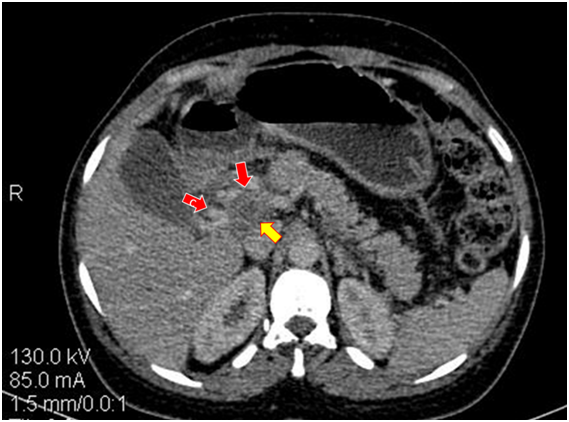

Figure 1Abdominal-pelvic scanner with portal time injection.

Portal thrombosis in the form of swelling with hypodensity of the portal trunk (yellow arrow); portal carvernoma (collateral venous circulation designated by the red arrows).